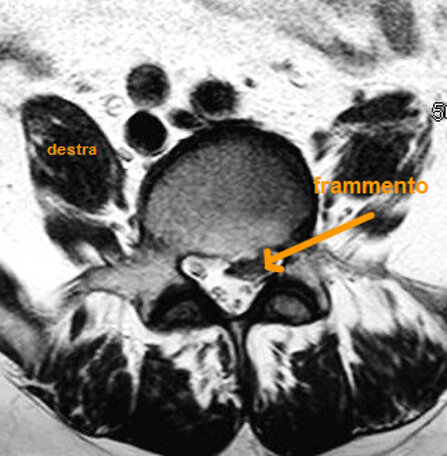

Il signore presentava intensa lombalgia e sciatalgia destra intensa e invalidante, tale da costringerlo a letto, con grave disagio di ogni attività sociale e impossibilità assoluta a svolgimento dell'attività lavorativa.

Nella scala soggettiva del dolore [VAS] che va da 0 (assenza di dolore) a 10 (dolore insopportabile e estremamente intenso), il signore riferiva una iniziale VAS di 8-9.

Gli veniva prescritta esecuzione di risonanza magnetica della colonna lombare. Effettuava alcune sedute di scramblertherapy, con associata terapia antidolorifica e anti-infiammatoria. La VAS (il dolore) migliorava e scendeva da 8-9 a 6-7.

Ciò consentiva una più agevole esecuzione della risonanza magnetica, che evidenziava una voluminosa ernia discale espulsa L5-S1 destra.

Eseguiva 15 sedute di ozonoterapia eco guidata sulla focalità erniaria.

La regressione del dolore è stata lenta e progressiva, con graduale discesa della VAS a 0-1.

Il signore beneficiato di un recupero del contesto familiare, ha potuto riprendere la normale attività lavorativa e sociale e sportiva non agonistica.

A distanza di 4 mesi ha effettuato una nuova risonanza magnetica lombare, che ha documentato la completa scomparsa della voluminosa ernia.

Secondo i criteri della medicina moderna non si può affermare con assoluta certezza che l’ozonoterapia eco guidata sia stata la causa diretta ed esclusiva della scomparsa dell’ernia, tenendo anche conto che la regressione di un’ernia discale può essere un fenomeno naturale e spontaneo.